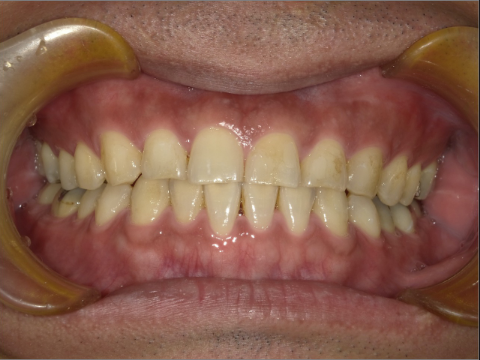

ご年齢 15歳女性 治療期間 2022/07/02〜2023/12/02(1年5ヶ月)

診断 110,000円(税込) アライナー 660,000円(税込) リテーナー 55,000円(税込)

ご年齢 15歳女性

治療期間 2022/07/02〜2023/12/02(1年5ヶ月)

診断 110,000円(税込)

アライナー 660,000円(税込)

リテーナー 55,000円(税込)

BEFORE

AFTER